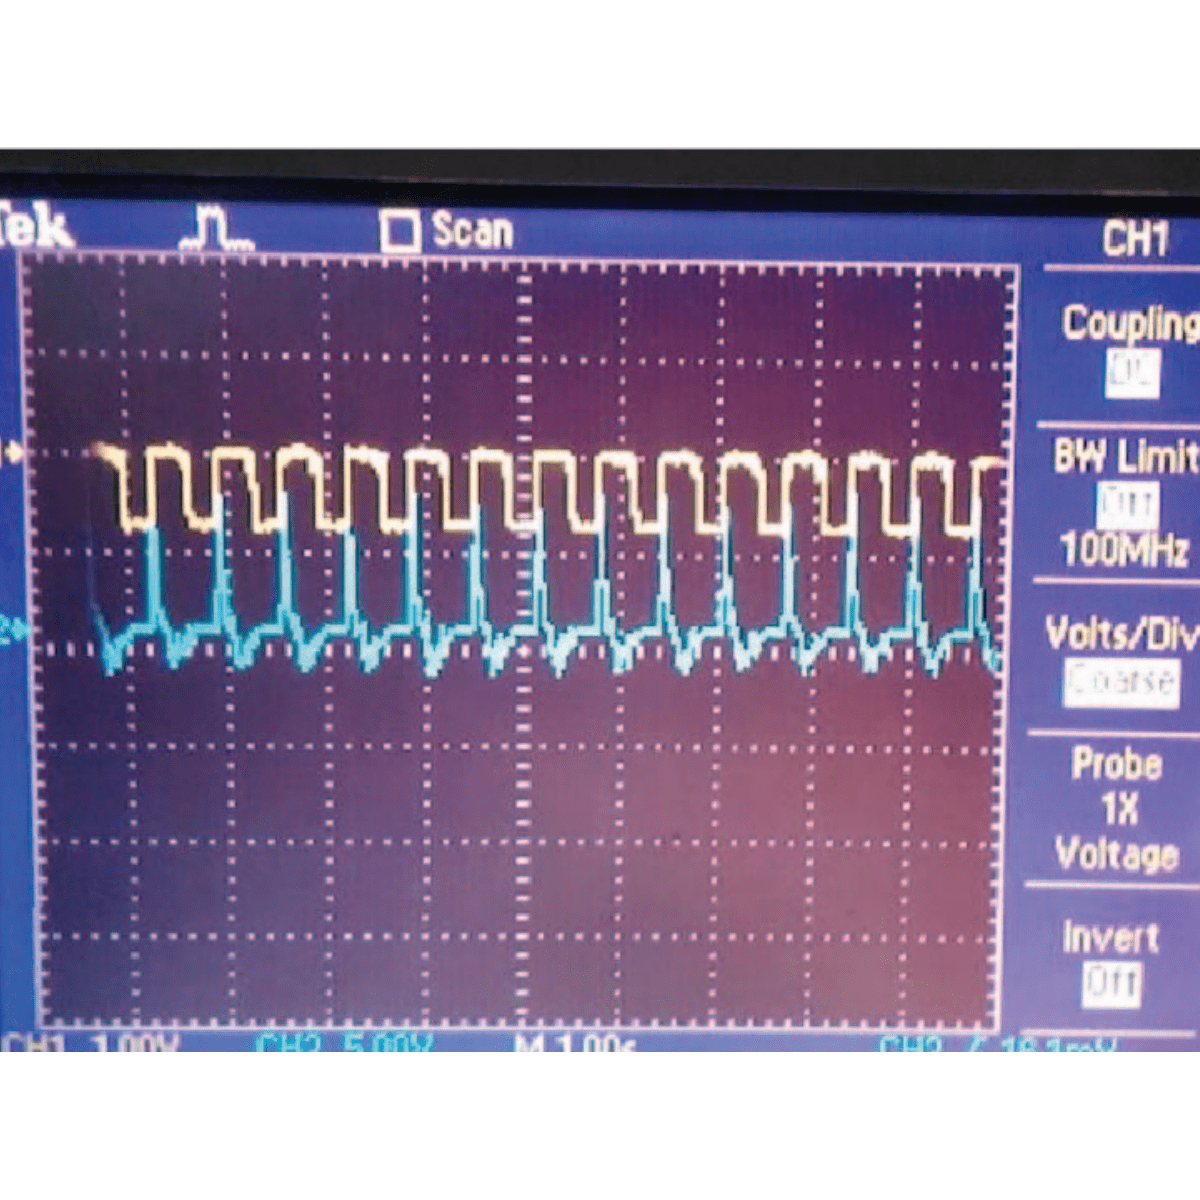

Non-Invasive Measurement of Heart Rate and Hemoglobin Concentration through Fingertip

This paper proposes a low cost method for the estimation of blood parameters using photo-plethysmography (PPG) technique. Data is obtained non-invasively from the fingertip, which is processed to estimate the heart rate and the hemoglobin concentration. The signal received from fingertip is first processed via analog filters and the output is sent to a computer through a microcontroller interface to be processed using MATLAB in order to estimate the parameters. The proposed method can be used for health monitoring purposes in rural areas. Furthermore, this solution could be ported to work on a standalone device, thus eliminating the need for a computer.